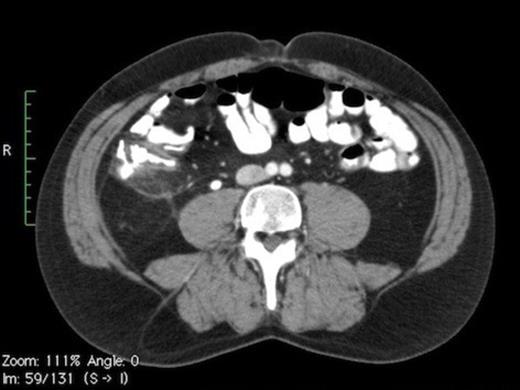

Contrast CT (Fig. 1A) depicts a thickened appendix measuring >12mm with periappendiceal fluid suggestive of acute appendicitis. Moderate hydronephrosis (Fig. 1C) of right kidney was noted with a 6mm calculus (Fig. 1B) in the right mid ureter.